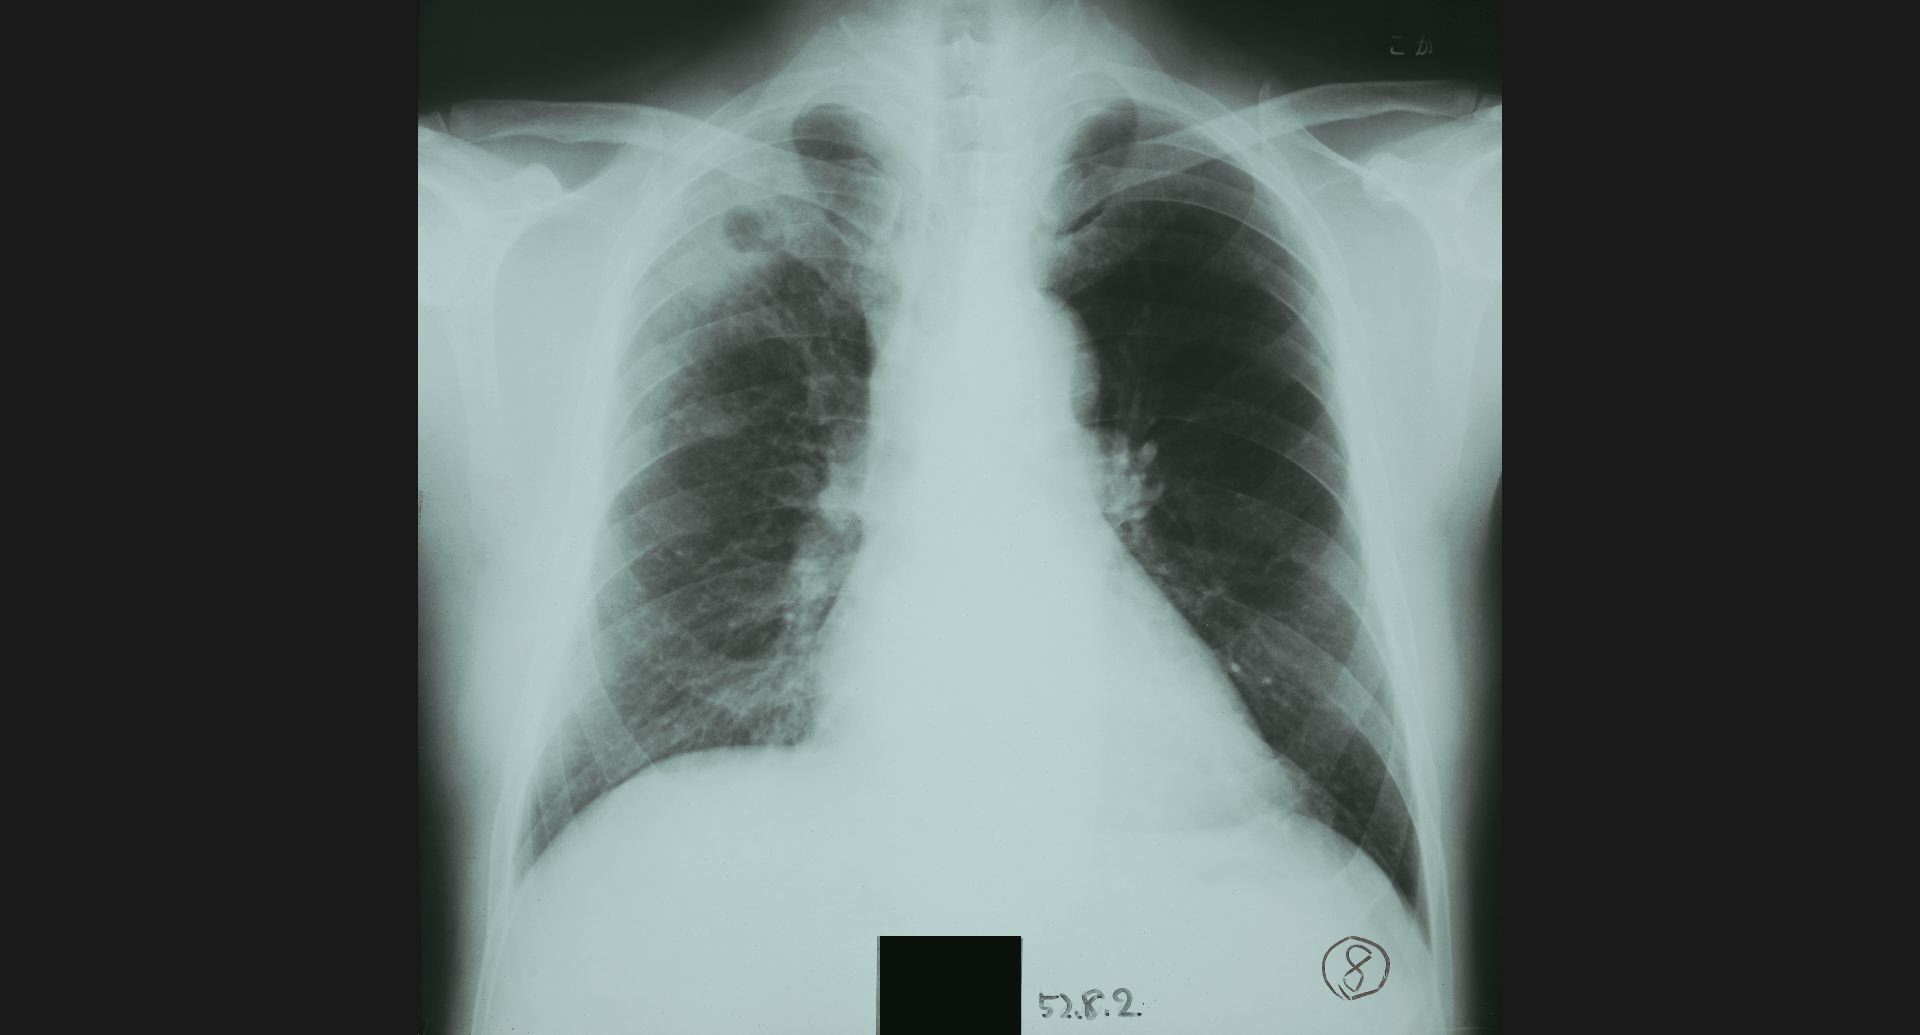

:Pneumoconiosis細かい斑状陰影。

fig.10(99KB)